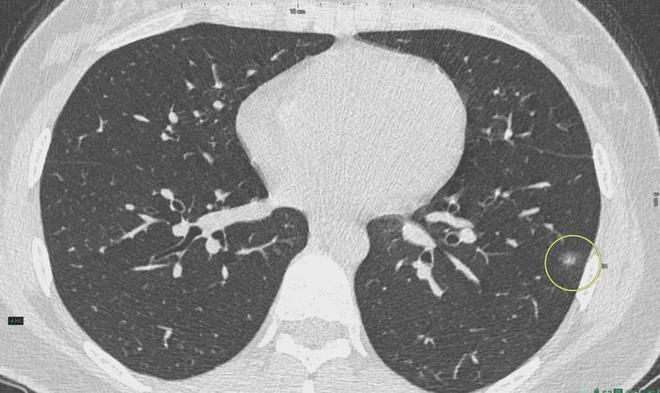

肺結節(jié)是一種常見的肺部疾病,其發(fā)病率逐年上升,雖然肺結節(jié)多數(shù)情況下是良性的,但也有可能惡化為肺癌,了解肺結節(jié)的形成原因?qū)τ陬A防和治療具有重要意義,本文將為您詳細解析肺結節(jié)的形成機制。